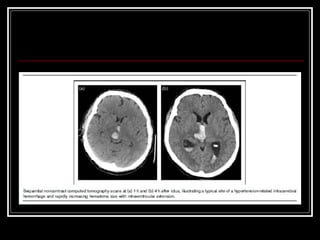

Diagnóstico TC de crânio sem contraste na fase aguda do evento  Limitações: Infratentorial tronco Outros: Lobar? Idade < 45 anos?Hemoventrículo solitário?Sem HAS? RNM e suas variações, arteriografia, etc. para investigação da etiologia do sangramento HDA e HPP (trauma? Anticoagulação? Drogas? Dça hematológica)

Diagnóstico TC decrânio sem contraste na fase aguda do evento Limitações: Infratentorial tronco Outros: Lobar? Idade < 45 anos?Hemoventrículo solitário?Sem HAS? RNM e suas variações, arteriografia, etc. para investigação da etiologia do sangramento HDA e HPP (trauma? Anticoagulação? Drogas? Dça hematológica)